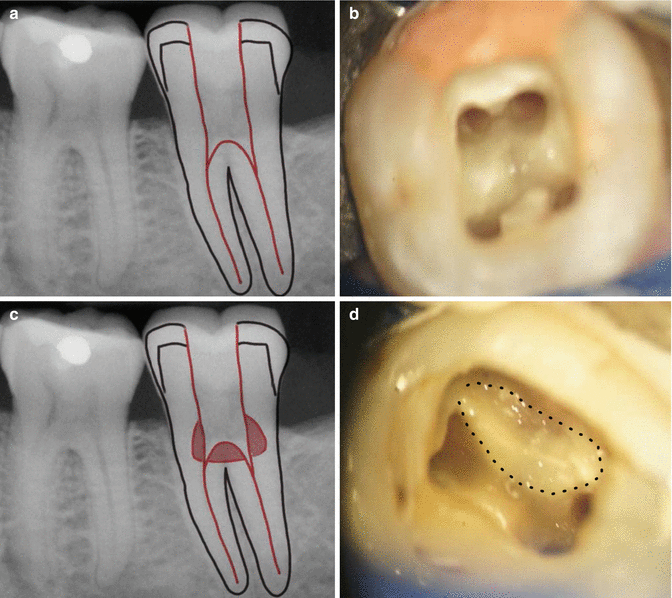

Iatrogenic Perforations Pocket Dentistry Types Of Endodontic Perforation  A perforation is a communication that arises between the periodontium and the root canal space. The reported rate ranges from 1% to 3% (kerekes. (aae glossary) accidental root perforations, which may. More coronally positioned perforations threaten the sulcular. Root perforation is an artificial communication between the root canal system to the supporting tissues of teeth or to the oral cavity.. Types Of Endodontic Perforation.

Figure 1 from Avoiding perforations in endodontics. Semantic Scholar Types Of Endodontic Perforation  Perforations are characterized according to their location: A small root perforation, sealed immediately and apical to the crest bone and epithelial attachment, presents with a better. Root perforation is an artificial communication between the root canal system to the supporting tissues of teeth or to the oral cavity. The reported rate ranges from 1% to 3% (kerekes. More coronally positioned. Types Of Endodontic Perforation.